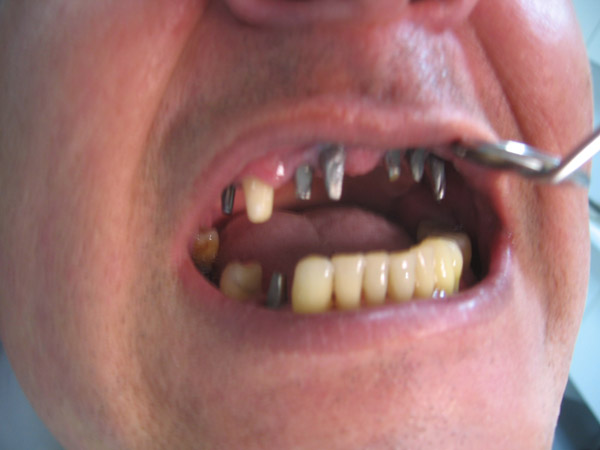

"Je suis très content des soins qui m'ont été prodigués par le Dr Manu et je ne peux que vous le conseiller fortement. Moi j'ai pay pour chaque implant 550 Euros et 190 Euros par couronne du porcelaine sur métal qui on été fait par des prothésistes qui sont à 2mn en voiture du cabinet du centre ville (Il en a deux et selon les soins vous allez à l'un ou à l'autre) et souvent il m'a prodigué des soins gracieusement. En france ou autour on aurait multiplié la facture par 2 au moins."